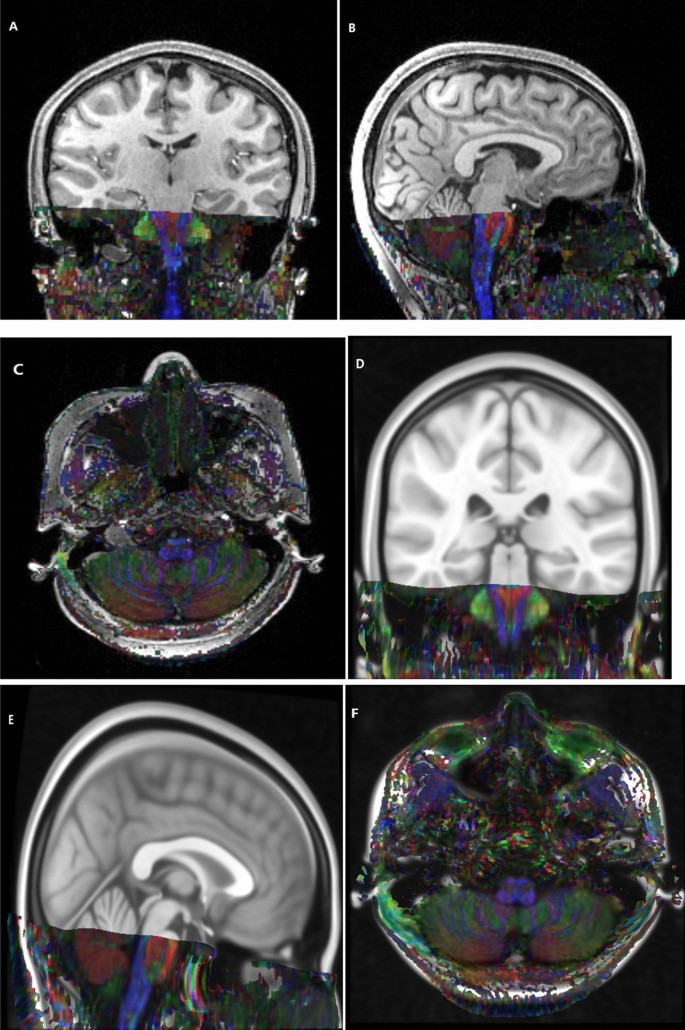

To construct group-level common template space of 0.4 mm3 voxel size, the 0.5 mm3 voxel of MNI152_T1_0.5 mm brain template (International Consortium for Brain Mapping) was normalized and resampled to 0.4 mm3 template using the "old norm" method of SPM12, which named MNI152_T1_0.4 mm template in the present study (Fig. 1). By using FSL-maths, a group of 4 common spherical seed regions (5 mm in diameter) was calculated and placed on the mastoid segment of intratemporal facial nerves, bilaterally and symmetrically (Fig. 2).

In this study, the raw RESOLVE data were resampled to 0.4 mm3 voxel size by performing affine transformation and nonlinear registration in the common MNI152_T1_0.4 mm space (Fig. 1). The resampled RESOLVE data were used to track the intratemporal facial nerve fibers of each subject in the 0.4 mm3 group-level common space, and the MPMs of the different group were obtained (Fig. 4). To observe the microscopic differences of intratemporal facial nerve fibers, the DTI indexes based on the different MPMs nerve were extracted.